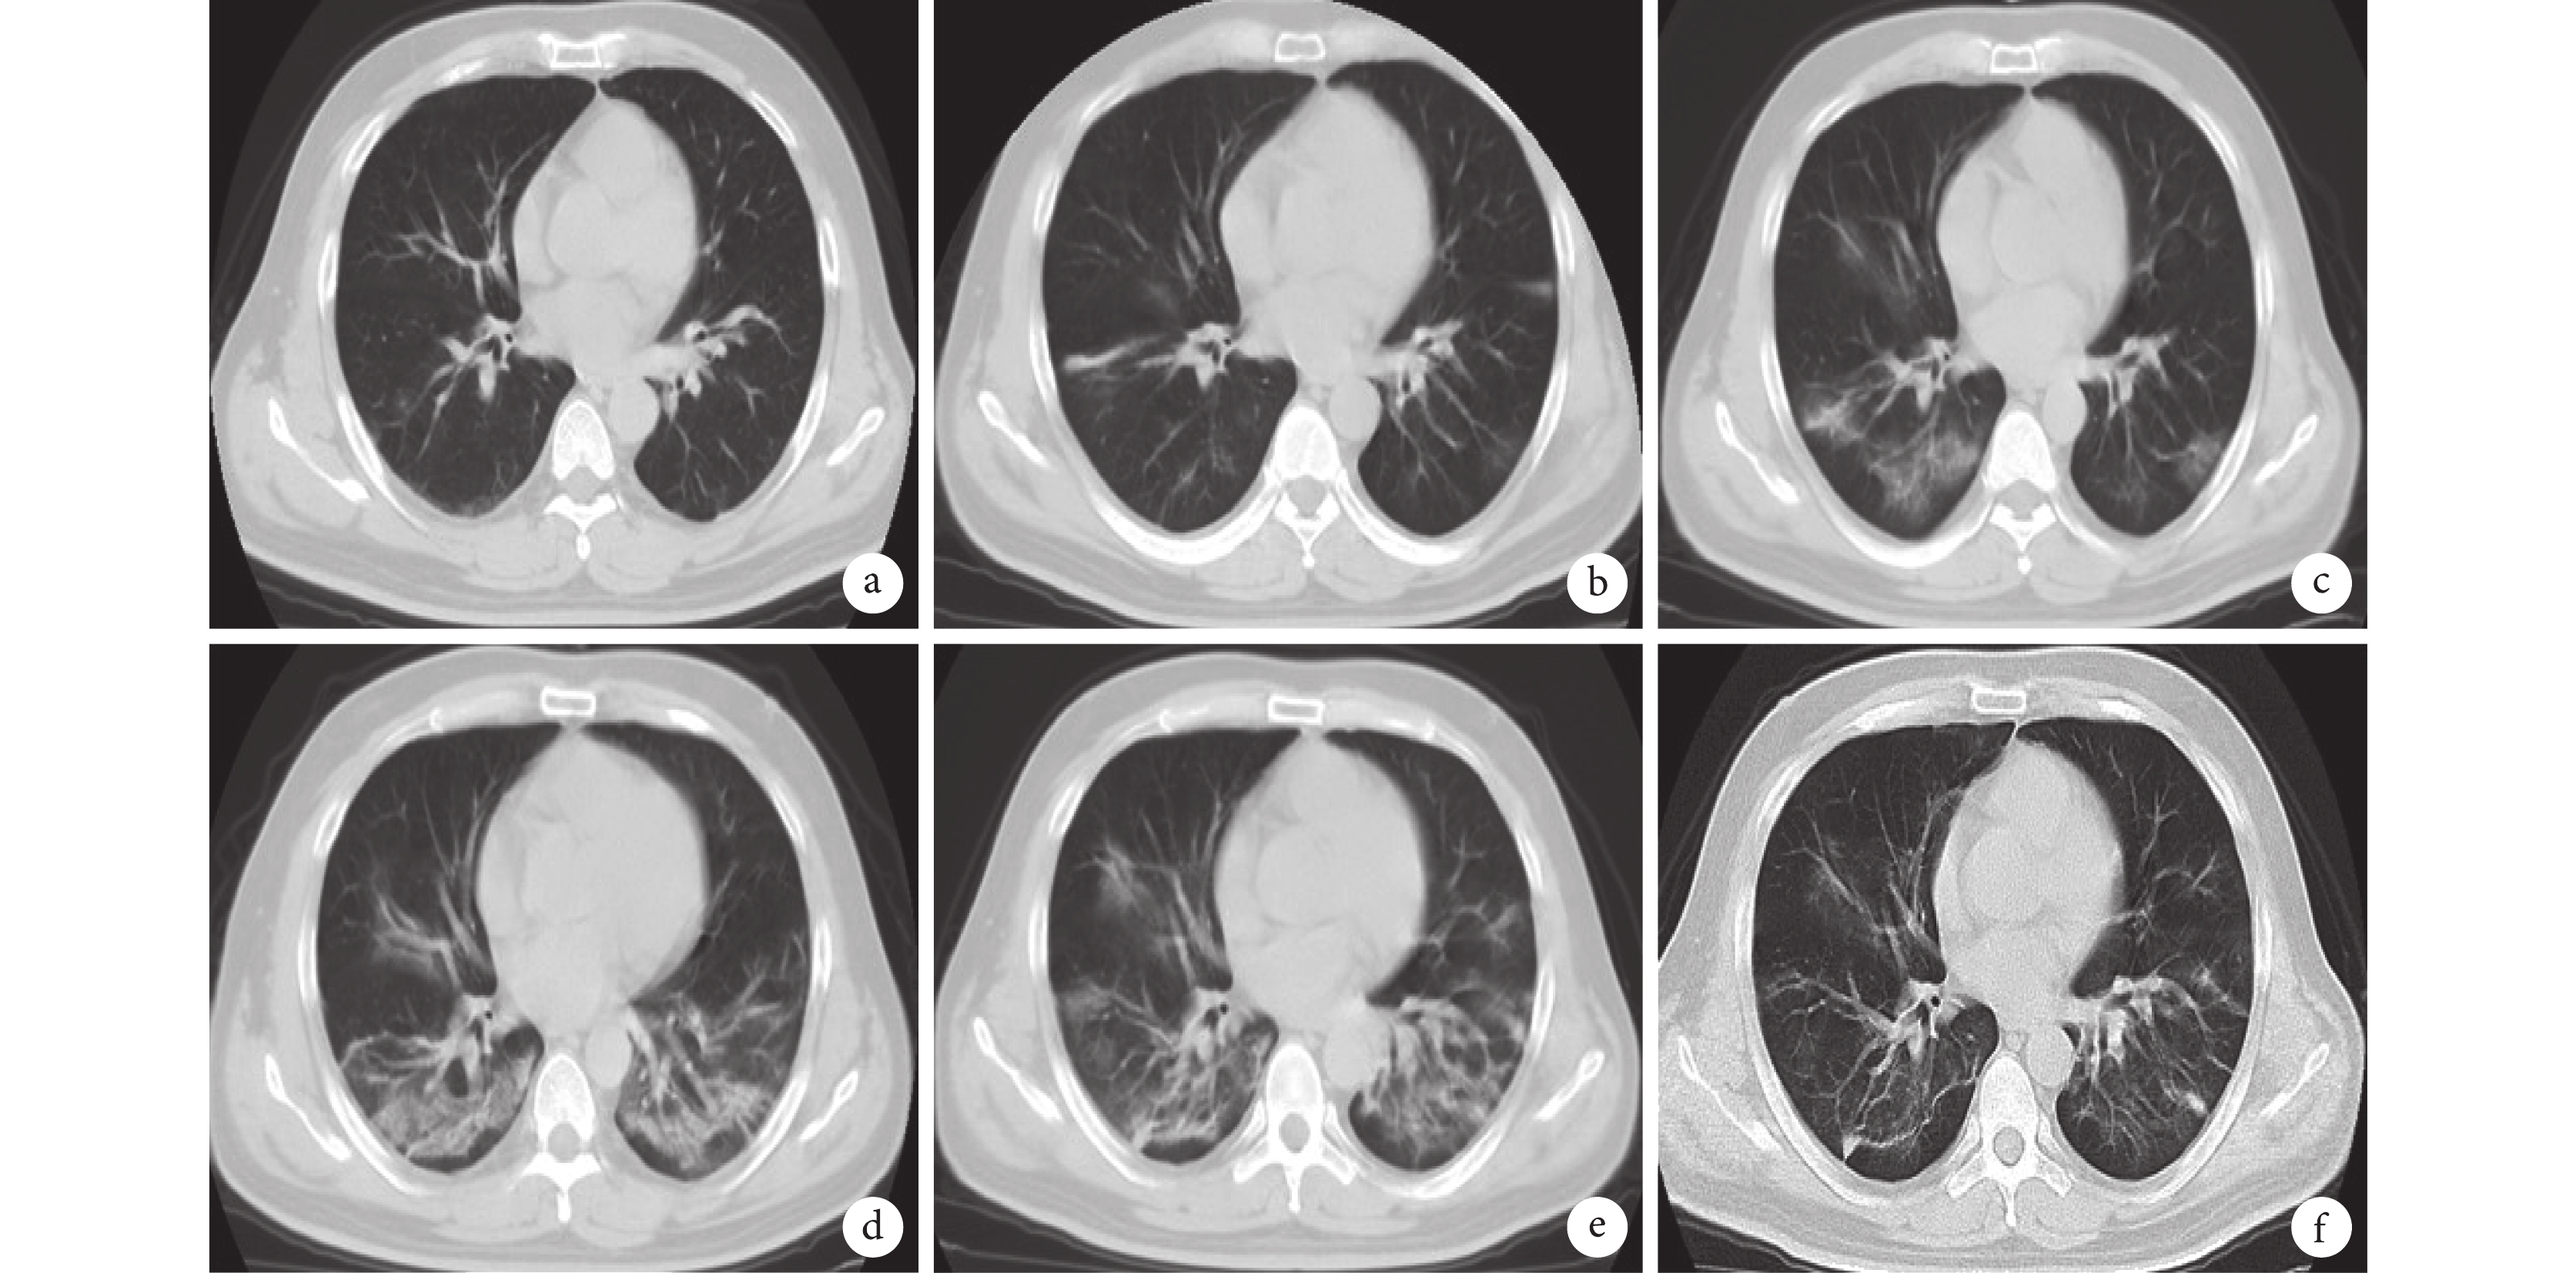

a. 入院當日(1 月 23 日);b. 入院第 3 天(1 月 25 日);c. 入院第 5 天(1 月 27 日);d. 入院第 7 天(1 月 29 日);e. 入院第 10 天(2 月 1 日);f. 入院第 16 天(2 月 7 日)。主要特點是快速進展的雙肺多發磨玻璃樣滲出病灶、部分實變,雙下肺病變為甚,后期病灶吸收出現纖維條索影

患者入院前 2 天(1 月 21 日)出現發熱、畏寒、咽痛、頭痛、咳嗽伴咳少量黃色膿痰,體溫最高達 38.7 ℃,無明顯喘息、呼吸困難,無咳血、胸痛、四肢骨關節疼痛等癥狀,自行服用酚麻美敏、羅紅霉素等藥物后體溫可降至正常,但很快反復。入院前 1 天(1 月 22 日)上述癥狀加重,至我院發熱門診就診。急查血常規未見明顯異常,胸部 CT 平掃見雙肺多發磨玻璃樣滲出影(圖 1a),結合患者流行病學史,考慮新冠肺炎可能性大,遂收入隔離病房治療。

入院第 1~3 天(發病第 3~5 天),患者咳嗽、咳少量黃色膿痰,伴活動后呼吸困難,持續高熱(最高 39.6 ℃),雙肺未聞及明顯干濕啰音。輔助檢查降鈣素原 0.024 ng/mL,隨機血糖 9.76 mmol/L,血氣分析 PaO2 62 mm Hg(1 mm Hg=0.133 kPa),余血常規、肝腎功、凝血未見明顯異常,甲流、乙流病毒核酸檢測陰性。胸部 CT 平掃見雙肺多發磨玻璃樣滲出影增多(圖 1b)。給予患者鼻導管吸氧(3 L/min),頭孢呋辛抗感染,利巴韋林抗病毒等治療,采集咽拭子予 SARS-CoV-2 核酸檢查。

入院第 4、5 天(發病第 6、7 天),患者呼吸困難、咳嗽咳痰癥狀持續加重,但峰值體溫降至 38.0 ℃ 以下。雙肺可聞及濕啰音。血常規示淋巴細胞低至 0.43×109/L,復查胸部 CT 見雙肺斑片滲出影較前明顯增加、超過原病灶 50%(圖 1c),血氣分析 PaO2 61 mm Hg,氧合指數小于 300 mm Hg,兩次 SARS-CoV-2 核酸檢查結果陽性。四川大學華西醫院專家遠程會診并依據《新型冠狀病毒感染的肺炎診療方案(試行第四版)》,該患者符合重型肺炎診斷標準。調整治療方案,給予 α-干擾素、洛匹那韋/利托那韋及胸腺法新抗病毒,甲潑尼龍抗炎,免疫球蛋白沖擊治療,頭孢呋辛升級為莫西沙星。

入院第 6、7 天(發病第 8、9 天),患者呼吸困難較前明顯加重,出現多尿多飲,淋巴細胞持續維持在低位 0.42×109/L,低氧血癥持續,糖化血紅蛋白 6.4%,餐后 2 小時血糖最高達 23.8 mmol/L,復查胸部 CT 見雙肺病灶繼續擴大,達全肺 1/3 以上,雙下肺出現實變(圖 1d)。專家組會診后建議將糖皮質激素量增加至 80 mg,加用高流量吸氧(10 L/min),予普通胰島素靜脈滴注降血糖。

入院第 8~10 天(發病第 10~12 天),患者呼吸困難癥狀逐漸緩解,峰值體溫降至 37.5 ℃ 以下。淋巴細胞數較前略增加,0.55 ×109/L,復查胸部 CT 見雙上肺病灶較前少量增加,雙下肺病灶部分吸收(圖 1e)。給予門冬胰島素及甘精胰島素后血糖控制差,餐后 2 小時血糖波動于 15~20 mmol/L。

入院第 11~14 天(發病第 13~16 天),患者呼吸困難、咳嗽較前明顯緩解,體溫恢復正常,淋巴細胞數恢復至 0.99 ×109/L,減量并停用甲潑尼龍,血糖基本恢復正常,入院第 16 天(發病第 18 天)復查胸部 CT 見病灶明顯吸收(圖 1f)。